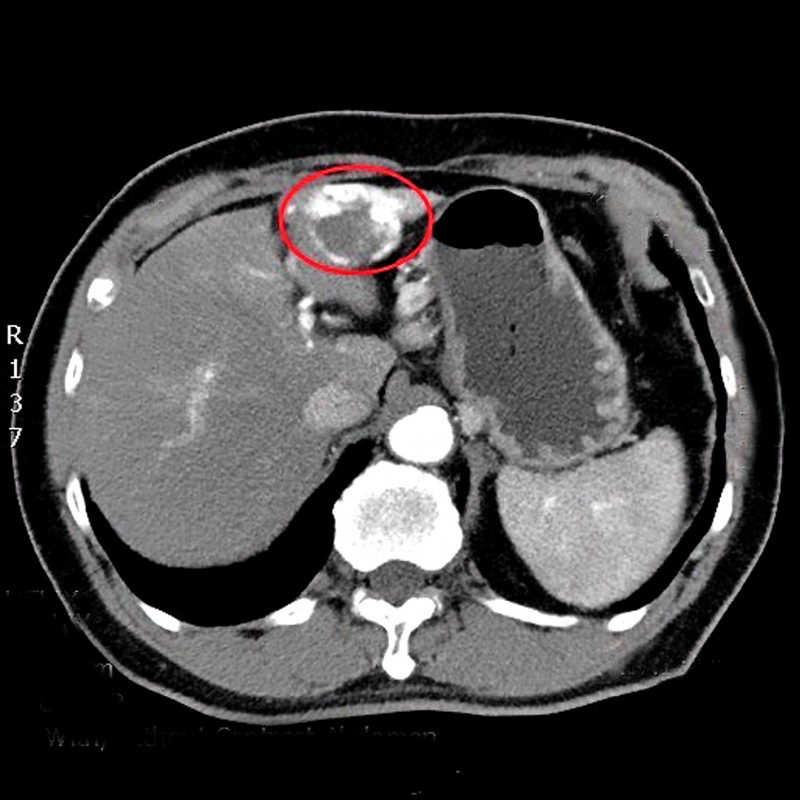

台中50歲林先生是B型肝炎帶原者,平時固定在診所抽血檢查追蹤,多年來數據正常,日前因血液中肝癌的腫瘤標記指數異常,轉介至醫院安排腹部肝臟超音波檢查,赫然在肝臟發現3公分大腫瘤,已是第2期肝癌,醫師提醒B型肝炎患者,要定期接受腹部超音波檢查,避免小病拖成大病。

台中50歲林先生是B型肝炎帶原者,平時有固定在診所抽血檢查追蹤,多年來數據都正常,直到日前因血液中肝癌的腫瘤標記指數異常,轉介至醫院進一步安排腹部肝臟超音波檢查,赫然在肝臟發現3公分大腫瘤,且已是第2期肝癌,醫師提醒B型肝炎患者,也要定期接受腹部超音波檢查,避免小病拖成大病。